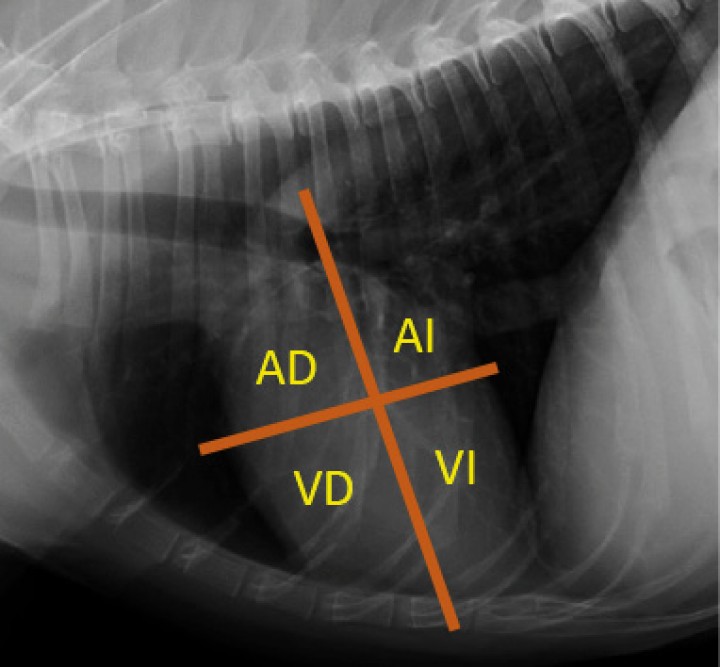

<p>Proyección lateral derecha con diagrama de la localización anatómica de las cuatro cámaras cardíacas. AD: atrio derecho. AI: atrio izquierdo. VD: ventrículo derecho. VI: ventrículo izquierdo.</p>

Proyección lateral derecha con diagrama de la localización anatómica de las cuatro cámaras cardíacas. AD: atrio derecho. AI: atrio izquierdo. VD: ventrículo derecho. VI: ventrículo izquierdo.